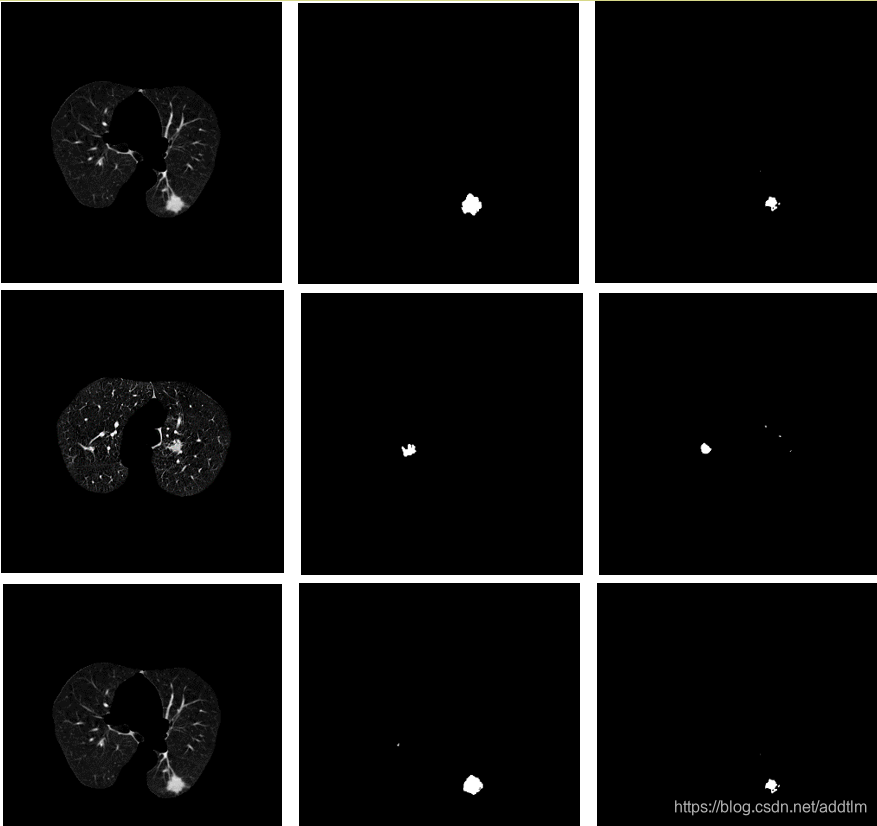

肺结节提取网络效果如下:

- 肺结节提取网络,用于从肺实质中提取出可疑肺结节,这个网络需要的数据集是肺实质图像(为了降低其他CT图像的影响)、以及对应的肺结节遮罩。使用的网络主要是Unet和一些改进过的Unet